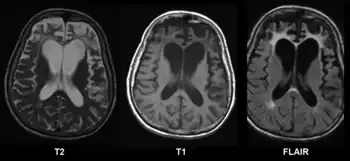

CT and MRI are most commonly used to observe the brain for cerebral atrophy. A CT scan takes cross sectional images of the brain using X-rays, while an MRI uses a magnetic field. With both measures, multiple images can be compared to see if there is a loss in brain volume over time.[20]

Difference from hydrocephalus

Cerebral atrophy can be hard to distinguish from hydrocephalus because both cerebral atrophy and hydrocephalus involve an increase in cerebrospinal fluid (CSF) volume. In cerebral atrophy, this increase in CSF volume comes as a result of the decrease in cortical volume. In hydrocephalus, the increase in volume happens due to the CSF itself.[20]